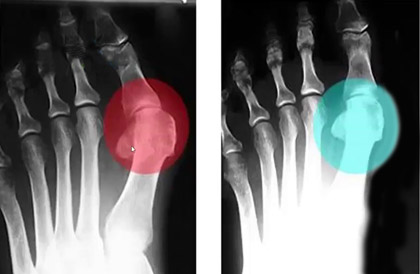

С целью устранения Hallus valgus (бурсита) и негативных симптомов, сопровождающих деформацию ступней, успешно применяется магнитотерапия. Магнитотерапия – уникальный метод физиотерапевтического лечения с помощью воздействия на организм постоянным, переменным или бегущим магнитным полем. Процедура является безопасной и не вызывает болезненных ощущений.

Чтобы купировать воспалительный процесс, достаточно использовать магнитную шину FootRelax ежедневно в течение 3-5 часов. Это способствует не только выравниванию фаланг пальцев и уменьшению деформации, но также благодаря воздействию магнитов происходит стимуляция нервных окончаний, повышается тонус тканей, улучшается кровообращение. FootRelax фиксирует большой палец в нужном положении, снижает нагрузку на ступни, купирует боль, облегчает ходьбу и возвращает здоровья ступням.